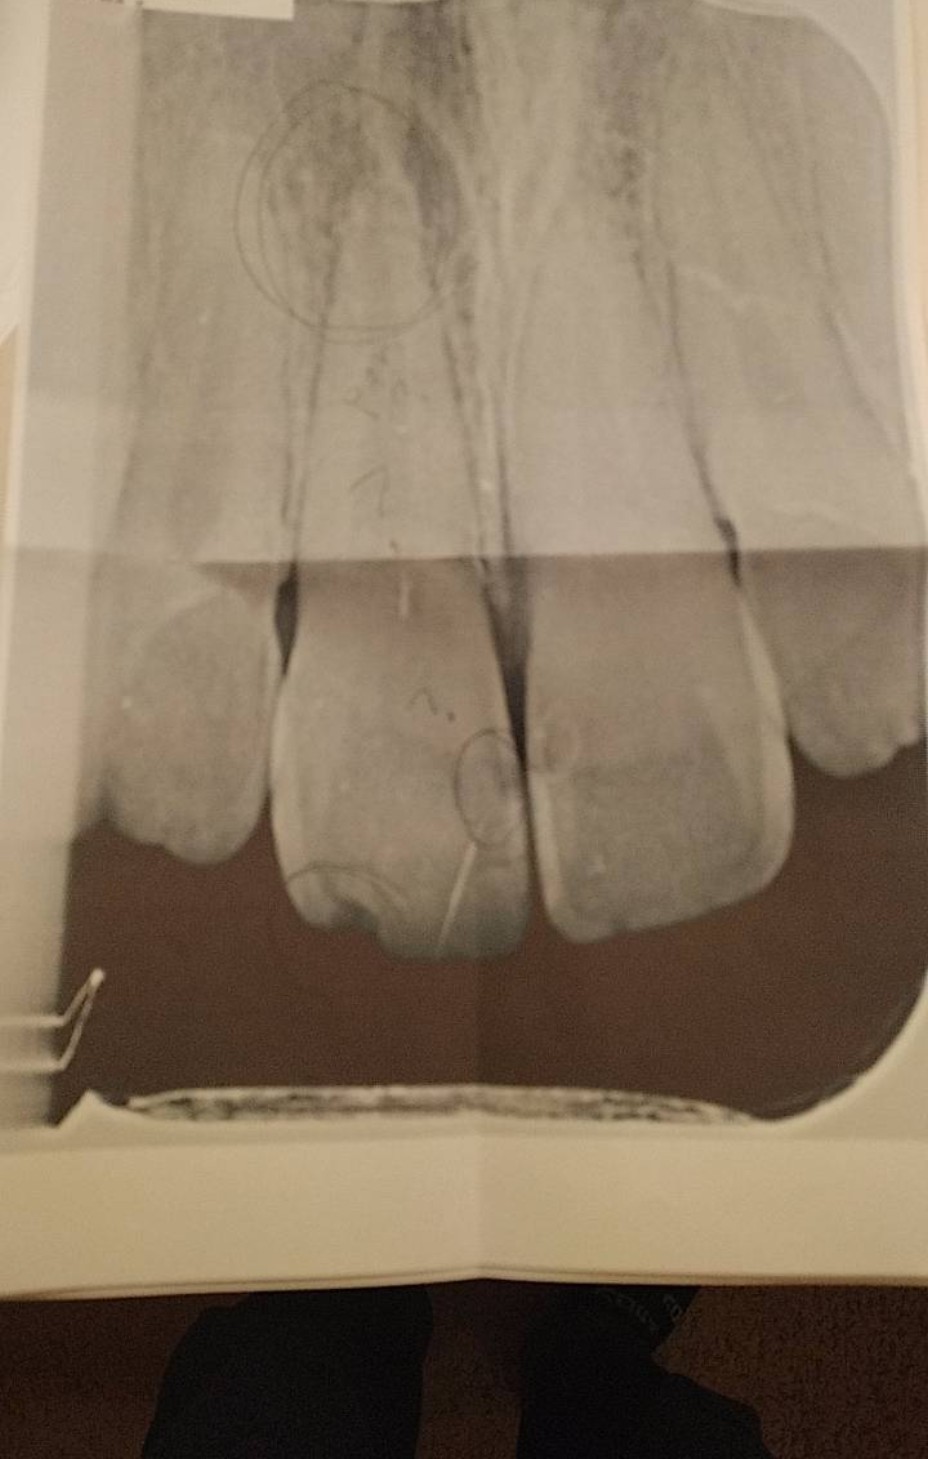

レントゲンを撮ると、 欠けた方の歯根の根元が黒くなっていて、これは炎症起こしているか虫歯が進行している、検査しないと詳しくは分からないとのこと。

レントゲン写真には手書きで per?と書かれていました。

根尖病巣の説明書をもらいました。